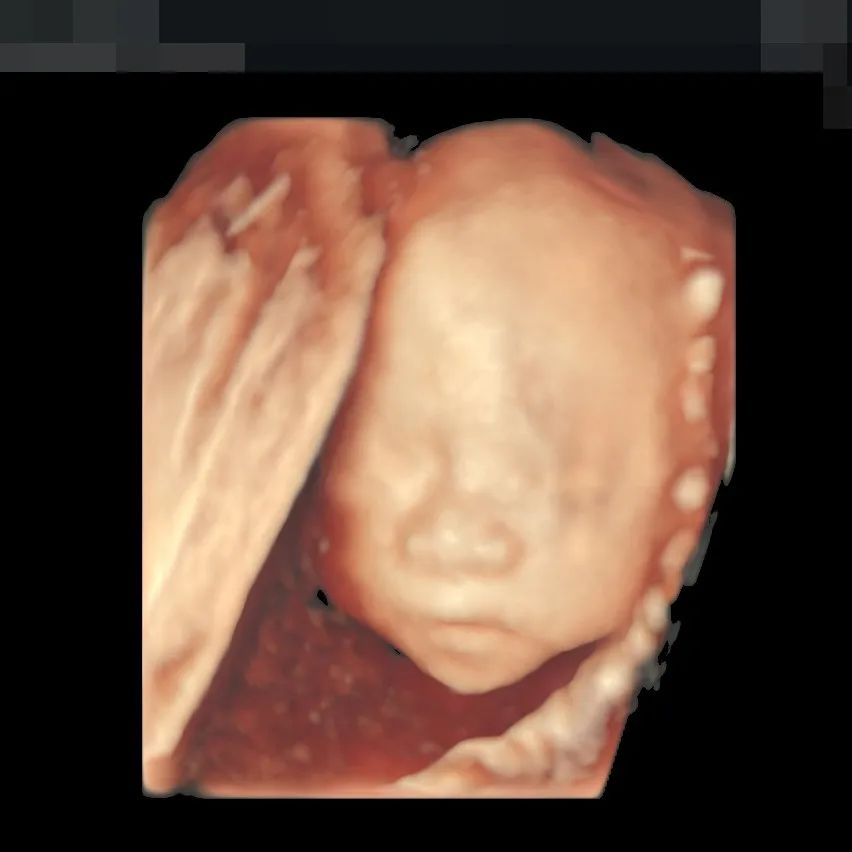

▲190斤孕妈王女士,不仅做了全面筛查,还留下了宝贵的胎儿影像,全家人都非常满意

超高清画质立体显示胎儿面部、脏器、四肢脊柱等发育情况,可高效筛查胎儿唇裂、骨骼发育异常以及中枢神经系统、呼吸系统、消化系统、泌尿系统、心脏的重大畸形。金标E10具备一整套胎心成像技术,支持从胎儿心脏结构到心功能的分析,可真实呈现胎心结构、脐带、血流变化,帮助临床医生及时作出诊断。“金标版”E10超真动态显示胎儿实时活动图像,画质全面颠覆传统视觉理念,堪比IMAX电影大片,让您看得更清晰、更直观。“金标版”GE-E10四维彩超,采用人体工程学设计,不存在射线、光波和电磁波等方面的辐射,对人体健康没有影响,孕妈妈们也可以安心检查。